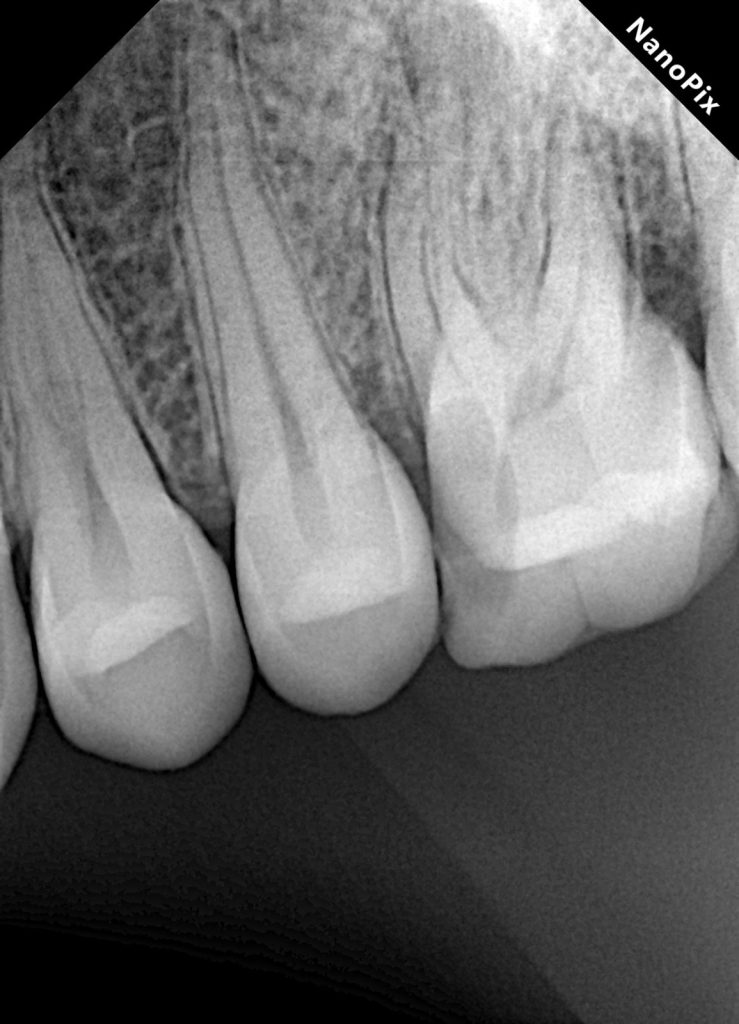

Clinical examination revealed a symptomatic maxillary molar with deep caries and compromised coronal structure. Vitality testing indicated irreversible pulpal pathology. Radiographic evaluation suggested complex canal anatomy with a high likelihood of an untreated MB2.

Conservative access preparation was performed with emphasis on visualization of the pulpal floor anatomy. The main mesiobuccal canal (MB1) was identified first, followed by careful exploration of the mesiobuccal groove.

Using magnification and tactile exploration, MB2 was located and negotiated. Canal patency was confirmed, and working lengths were established for all canals.

Following complete drying of the canal system, obturation was performed to achieve a dense, three-dimensional seal. All canals, including MB2, were obturated to full working length with confirmed radiographic adaptation.